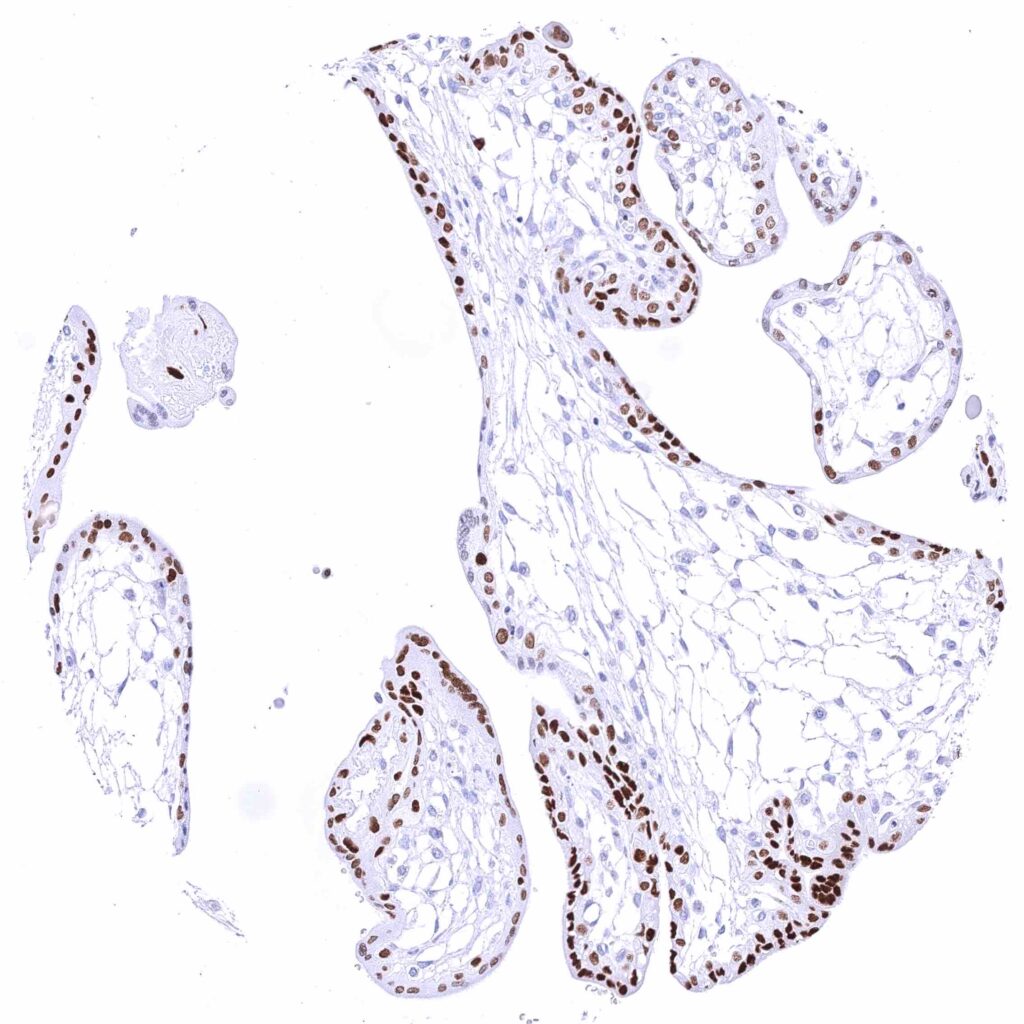

Kidney, pelvis, urothelium – Strong nuclear GATA3 positivity of all urothelial cells.